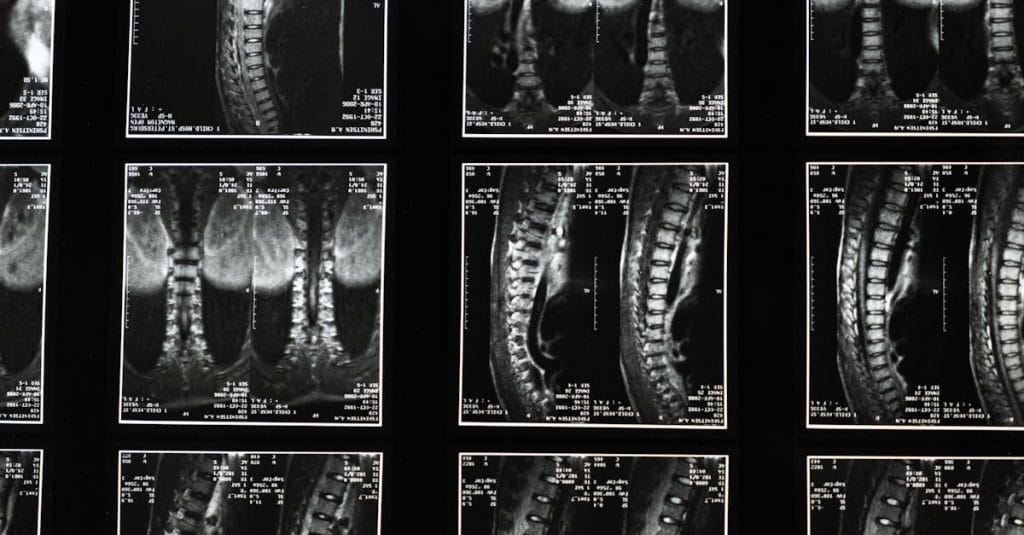

La décompression spinale est une thérapie non invasive qui traite divers troubles de la colonne vertébrale tels que les hernies discales, les douleurs lombaires ou la sciatique. En utilisant un appareil spécialisé, des forces de traction sont appliquées, permettant ainsi aux disques intervertébraux de retrouver leur position normale. Cette méthode aide à réduire la douleur et à améliorer la flexibilité et la mobilité de la colonne vertébrale.

La décompression spinale est une méthode non invasive qui consiste à appliquer des forces de traction sur la colonne vertébrale pour créer un espace entre les vertèbres. En réduisant la compression exercée sur les disques intervertébraux, cette technique aide à soulager la pression sur les nerfs et à réduire les douleurs. Avec un équipement spécialisé, la décompression peut aussi favoriser l’hydratation et la respiration des disques, favorisant ainsi leur guérison.

La décompression neurovertébrale est une méthode innovante et non invasive qui se spécialise dans le soulagement des douleurs liées à des pathologies discales sévères telles que les hernies discales et les sténoses. Grâce à une traction douce et contrôlée, cette technique permet d’étirer la colonne vertébrale, diminuant ainsi la pression sur les disques intervertébraux et les nerfs environnants. En créant une pression négative au sein des disques, elle favorise la rétraction du matériel discal hernié tout en améliorant la circulation sanguine. Ce processus joue un rôle crucial dans la guérison des tissus endommagés, rendant la décompression neurovertébrale particulièrement bénéfique pour les patients souffrant de douleurs chroniques au dos ou au cou.